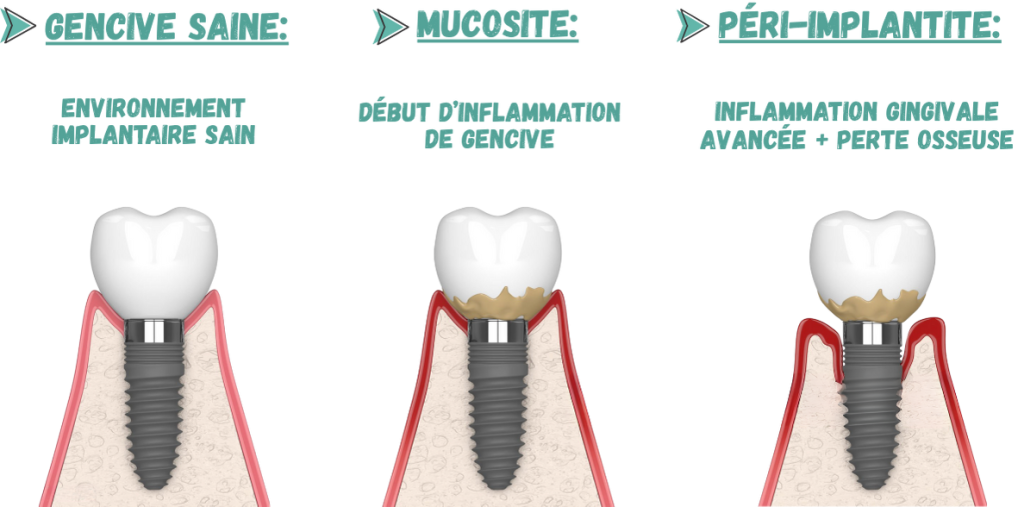

Greffe de la Gencive / Chirurgie Mucco-Gingivale

Renforce la gencive autour des implants afin d’avoir un environnement implantair sain favorisant la pérennité de l’implant dans le temps. Trois cas de figure : Avant la pose d’implant, Durant la pose d’implant, après la pose d’implants.